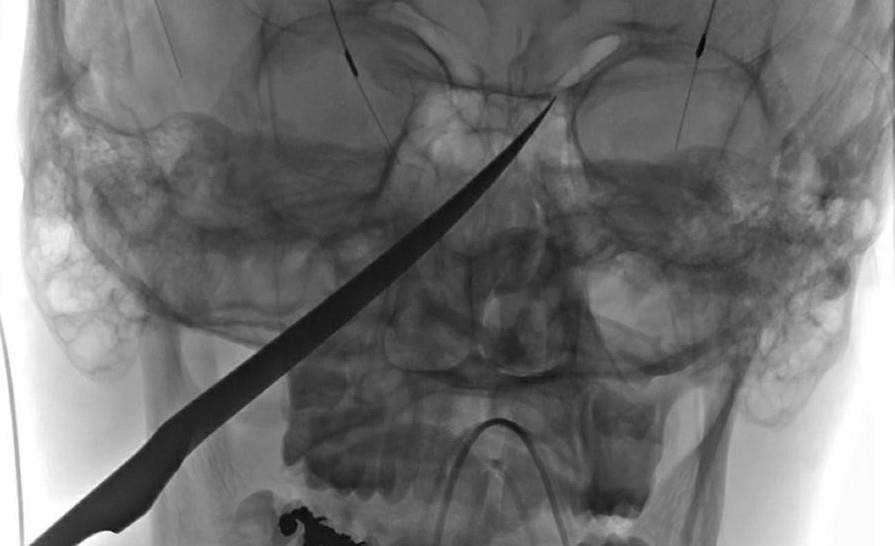

Một cậu bé đến từ bang Kansas, Mỹ, đang chơi thì bị con dao đâm xuyên vào mặt. Các bác sĩ nói rằng cậu cực kỳ may mắn mới có thể sống sót.